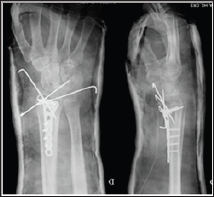

A 48 year-old male, caucasian, policeman, right handed, attended the emergency service due to right wrist pain and functional impotence. Five weeks earlier he had suffered a road accident resulting in a fracture of the distal right radius (AO subtype 23-B3) (Figure 1) and a tibial plafond fracture. At a foreign hospital that received him, he was submitted to radius osteosynthesis with an anatomic volar distal radius plate and in the lower right limb a temporary joint-bridging external fixation was placed during 1 week, and was posteriorly substituted by screws and plate fixation in the tibia and fibula. The wrist cast was removed 4 weeks after surgery in a private hospital in our country. After this episode he began to feel pain, without any history of associated trauma. He had no other previous history of interest. The physical examination revealed a "dinner fork” deformity, with a volar translation of the carpus. The skin was intact. There was no neurovascular deficit. Imaging showed a Dumontier type II volar radiocarpal dislocation (Figure 2A). At the emergency department we conducted closed reduction through traction after infiltration of a local intra- articular anesthetic, without success nevertheless (Figure 2B), so we decided to proceed to surgical treatment. Intraoperatively, through a volar approach of the radius, a bone fragment distal to the plate was visible. A dorsal approach was needed to reduce the dislocation. A radiocarpal fixation with three Kirschner wires was performed, two of them fixing the volar fragment of the distal radius, and one stabilizing the radiocarpal joint. One screw of the plate was removed due to its' intraarticular location. The distal radioulnar joint was evaluated under dynamic fluoroscopy and was apparently stable. Immediate postoperative radiographs confirmed a concentric reduction and stable fixation of the radiocarpal joint (Figure 3). Postoperatively, the patient was placed in an arm cast with free elbow and metacarpophalangeal (MP) joints. There were no perioperative complications. The immobilization and the kirschner wires were maintained for 7 weeks. After removing the cast and the kirschner wires, the patient presented flexion of 20°and extension of 15°, which improved up to flexion 30° and extension 60°, supination 60°, with preserved pronation, 24 months after the trauma. At this time, the patient reports no pain, feeling of instability or signs of nerve compression. The DASH disability score result was 3,1 and the Mayo Wrist Score was 93. The radiograph control did not show any relevant alteration (Figure 4).

Figure 3: Postoperative PA and lateral radiographs of the right wrist show maintained reduction of the radiocarpal joint after radiocarpal fixation with 3 Kirschner wires.